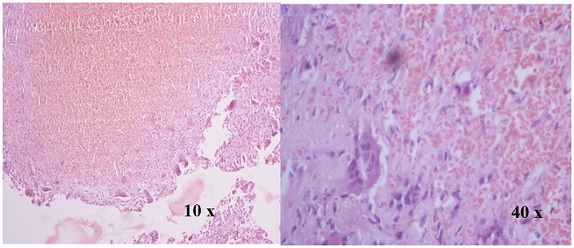

Figure 4 H&E Stained section show spaces separated by septa containing blood. Septa compose of osteoclast like giant cell and fibroblast (Aneurysmal bone cyst).

On histopathological examination aneurysmal bone cyst showed various cystic spaces separated by blood. Septation is one of the most important aspects of the aneurysmal bone cyst. These septa are composed of osteoclast like giant cell and fibroblast.